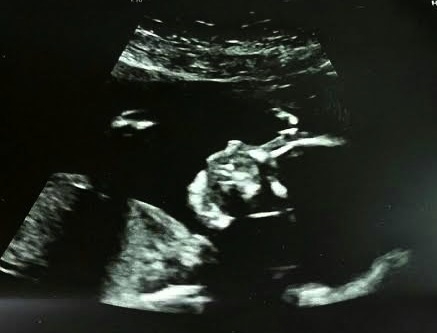

• Anatomy scan today @ 20 weeks.

OB said everything looks good, no concerns at this time.

Baby was belly down and did not want to flip over so the tech said "it might be a girl "

Seriously?  MIGHT be???  Aggravating but at 28 weeks they do another ultrasound where they give you more pics and make a little video of the baby moving around. She said she'll try checking then to see if baby is indeed a girl.